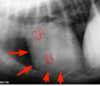

What abnormality is visible in the picture? (R303)

Intestinal obstruction

air swallowing

gastric torsion

gastric dilatation

gastric torsion